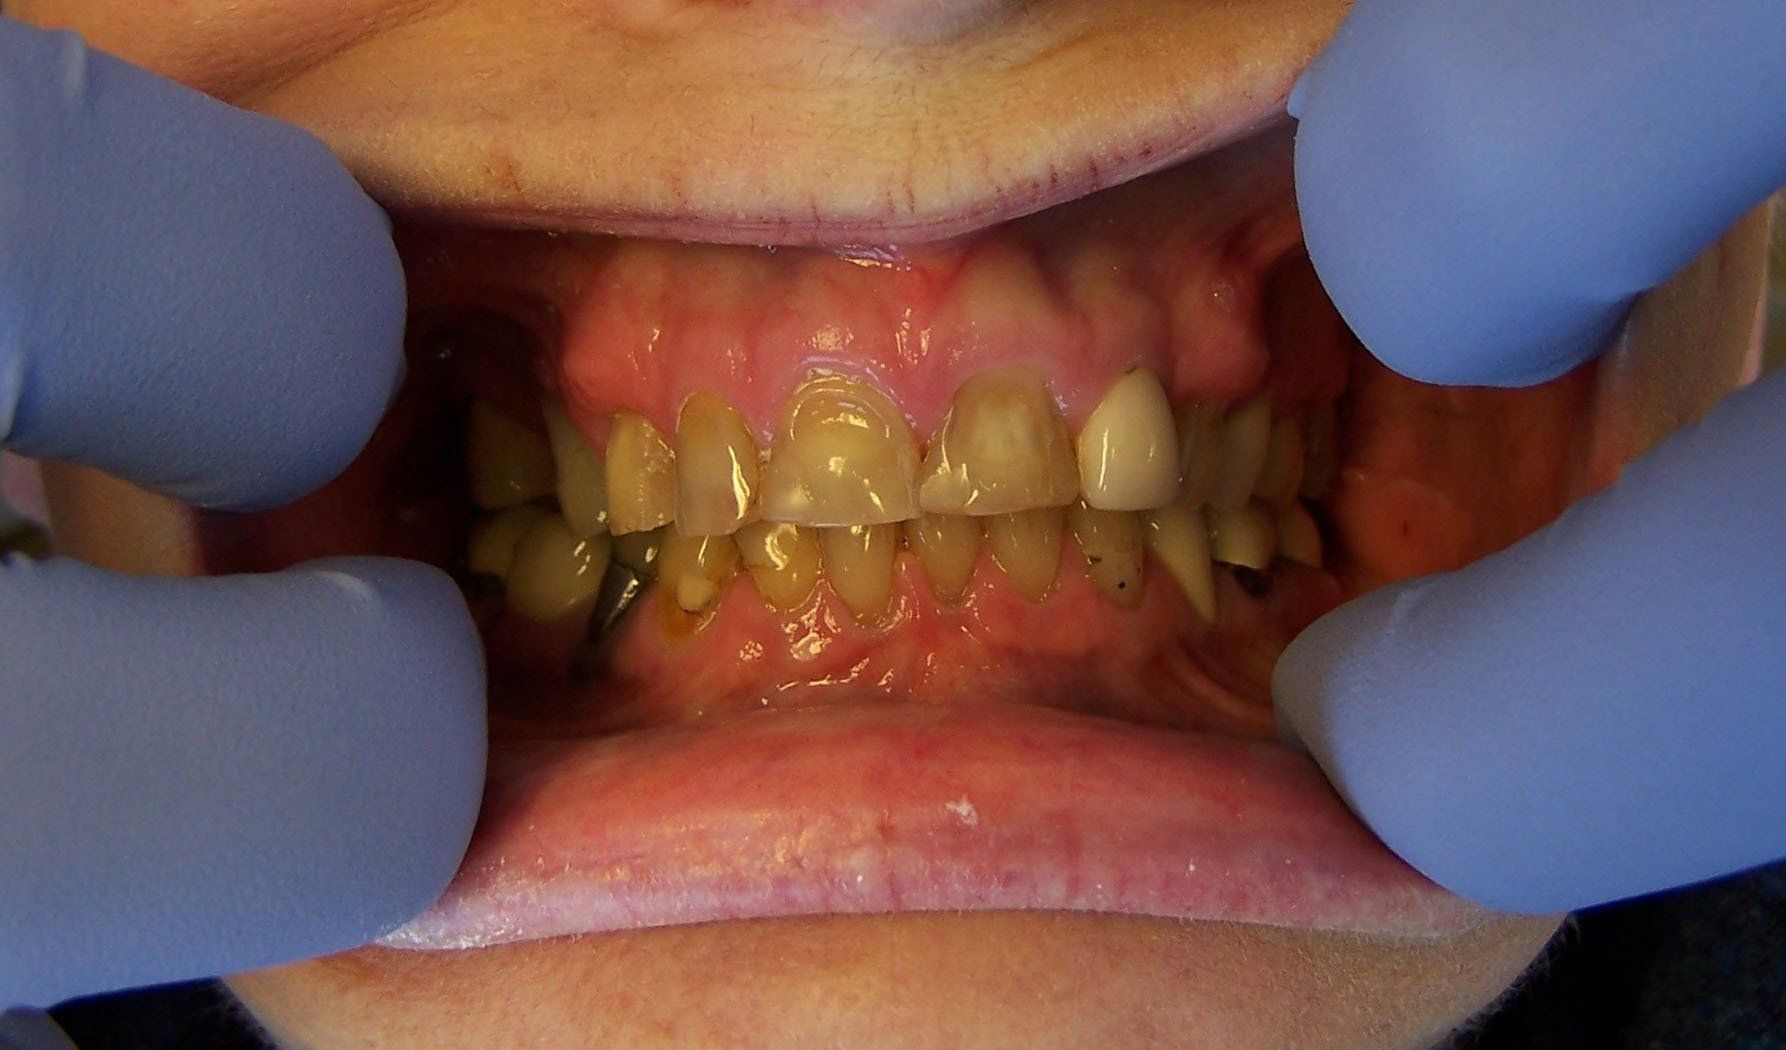

Johnson Before

Button

Johnson After